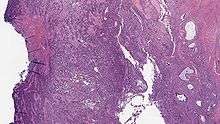

| Micrograph of a low-grade endometrial stromal sarcoma. H&E stain. | |

Low-grade endometrial stromal sarcoma consists of cells resembling normal proliferative phase endometrium, but with infiltration or vascular invasion. These behave more aggressively, sometimes metastasizing, with cancer stage the best predictor of survival. The cells express estrogen/progesterone-receptors.